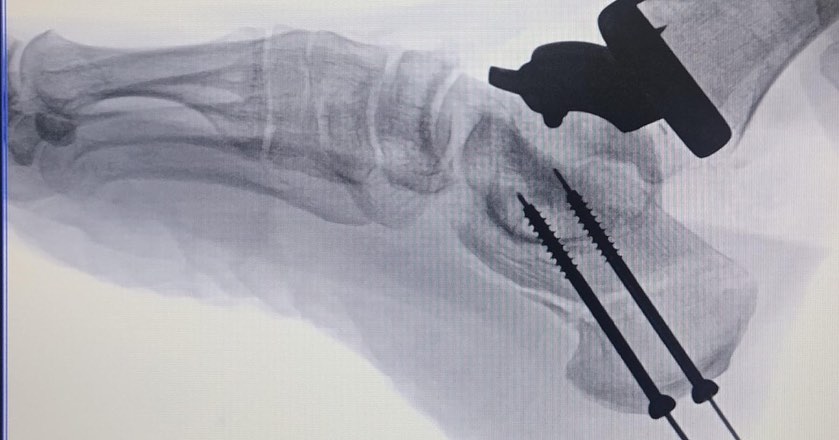

¿Qué es una osteotomía correctiva del calcáneo?

El calcáneo es el hueso más grande del tobillo y del pie. Una osteotomía correctiva del calcáneo implica realizar un corte en este hueso para realinearlo y corregir deformidades que causan dolor o inestabilidad en el tobillo.

Esta cirugía se utiliza para tratar condiciones como el pie plano, el pie cavo o las fracturas mal consolidadas del calcáneo.

¿Cuándo se combinan ambos procedimientos?

En algunos casos, tanto el reemplazo articular del tobillo como la osteotomía correctiva del calcáneo pueden realizarse en la misma cirugía. Esto suele ocurrir cuando el paciente presenta una combinación de artritis y deformidades en el tobillo.